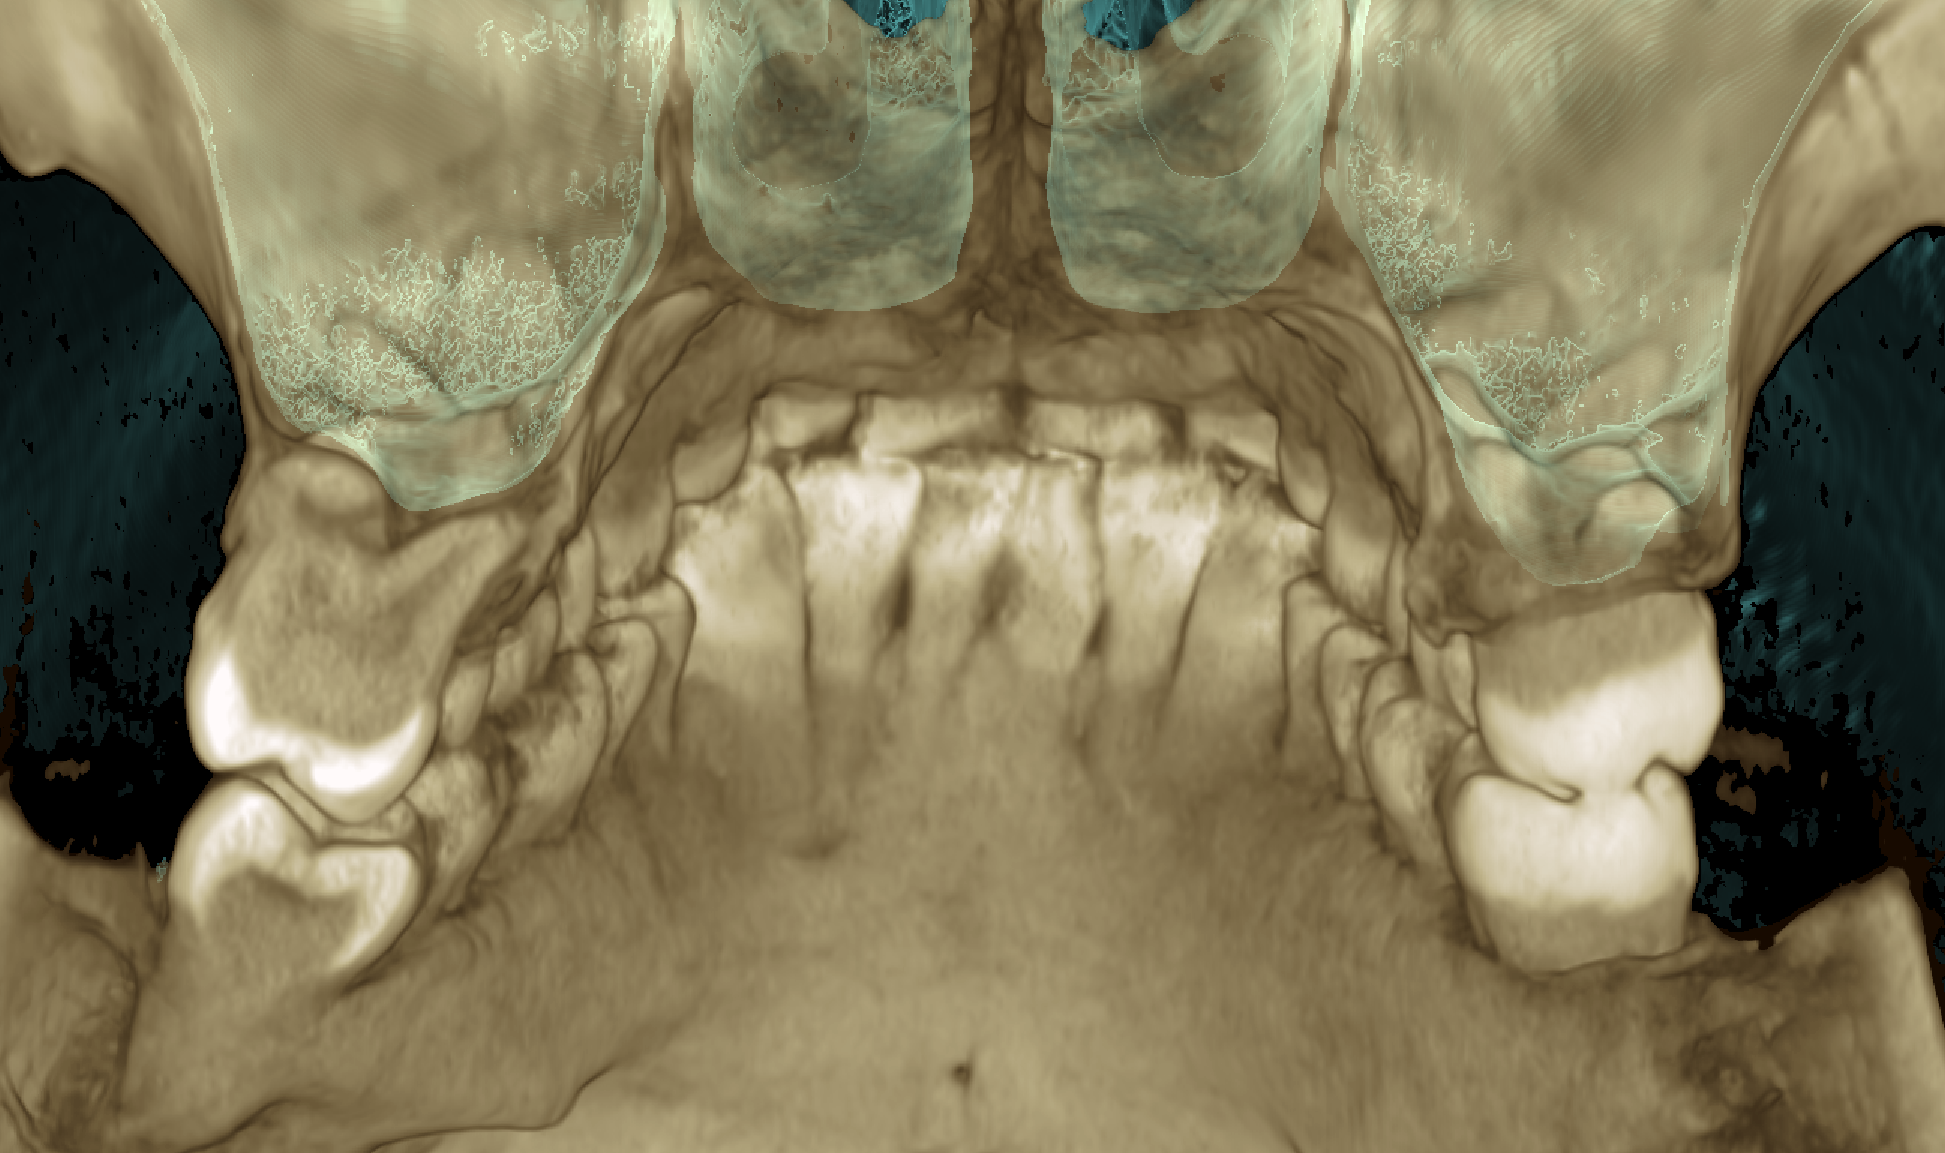

Сделал снимок своей челюсти, чтобы вам было лучше видно какой я унтерменш

Че за бородавка костная нахуй? Ты че ваще нахуй?

Мой рот изнутри

Сам в ахуе, тупа дырки сквозные. Может там нервы проходят?

Я тут какую-то гигапломбу нашёл. чзх

Чо восьмерочек слева не завезли?